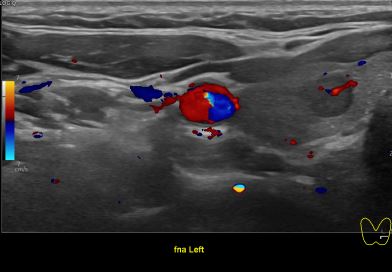

상기환자 외부건진 이상소견으로 추적검사위해 내원하신 30대 중반 여성분으로

의심스러운 갑상선 좌엽 세포검사후 갑상선암으로 진단되었습니다